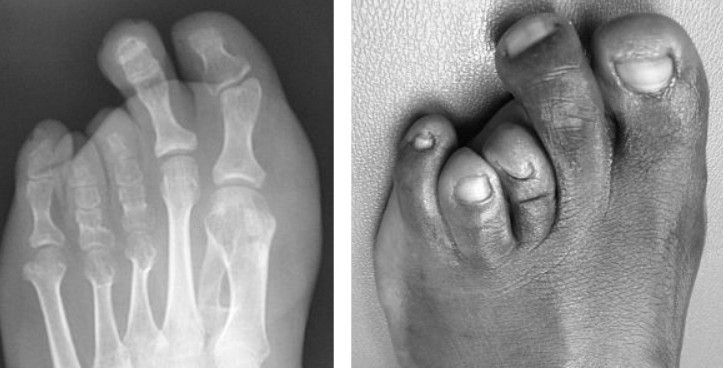

Geralmente, o dedo correspondente ao metatarso curto parece menor, mais retraído ou até "flutuante", sem o contato adequado com o solo. Isso acontece porque o osso que deveria empurrar o dedo para a frente não tem o comprimento esperado.

Na maioria dos casos, o osso mais afetado é o 4º metatarso (o que leva ao dedo anelar), mas a Braquimetatarsia pode ocorrer em qualquer um dos cinco metatarsos ou até mesmo em vários ao mesmo tempo.

- Dedos sobrepostos ou desalinhados: O dedo correspondente ao metatarso curto pode parecer retraído, levantado ("dedo flutuante") ou até mesmo sobrepor os dedos vizinhos, o que pode levar a atritos e dor.

Sim, a Braquimetatarsia frequentemente causa um impacto estético significativo, sendo essa uma das principais razões que levam as pessoas a buscar tratamento. A aparência do pé pode mudar bastante, com o dedo afetado parecendo mais curto, retraído ou "flutuante" em relação aos outros.

O que causa essa alteração visual?

Quando o metatarso é mais curto, o dedo que ele sustenta não se estende até a linha dos outros dedos. Isso cria um espaço anormal ou faz com que o dedo pareça "pendurado" ou elevado em comparação aos outros, perdendo o contato com o solo e muitas vezes se tornando rígido.

- Radiografias (Raios-X): São essenciais. As radiografias fornecem imagens claras dos ossos do pé, permitindo ao médico medir o comprimento exato de cada metatarso e compará-los, confirmando o diagnóstico de Braquimetatarsia. Também ajudam a avaliar a angulação e o alinhamento dos ossos.